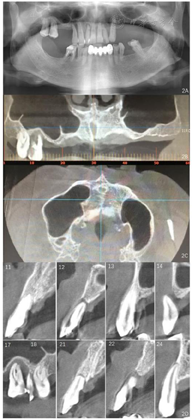

影像学检查:曲面体层片及CT检查显示11、21牙槽骨吸收至根尖1/3;12、14、17、22牙槽骨吸收超出根尖,12、22根尖圆形低密度影像,17根尖周低密度影像;18、13、23、35、45、46牙槽骨吸收至根长2/3;37近中及远中邻面可见低密度透射影像,近髓(图2)。